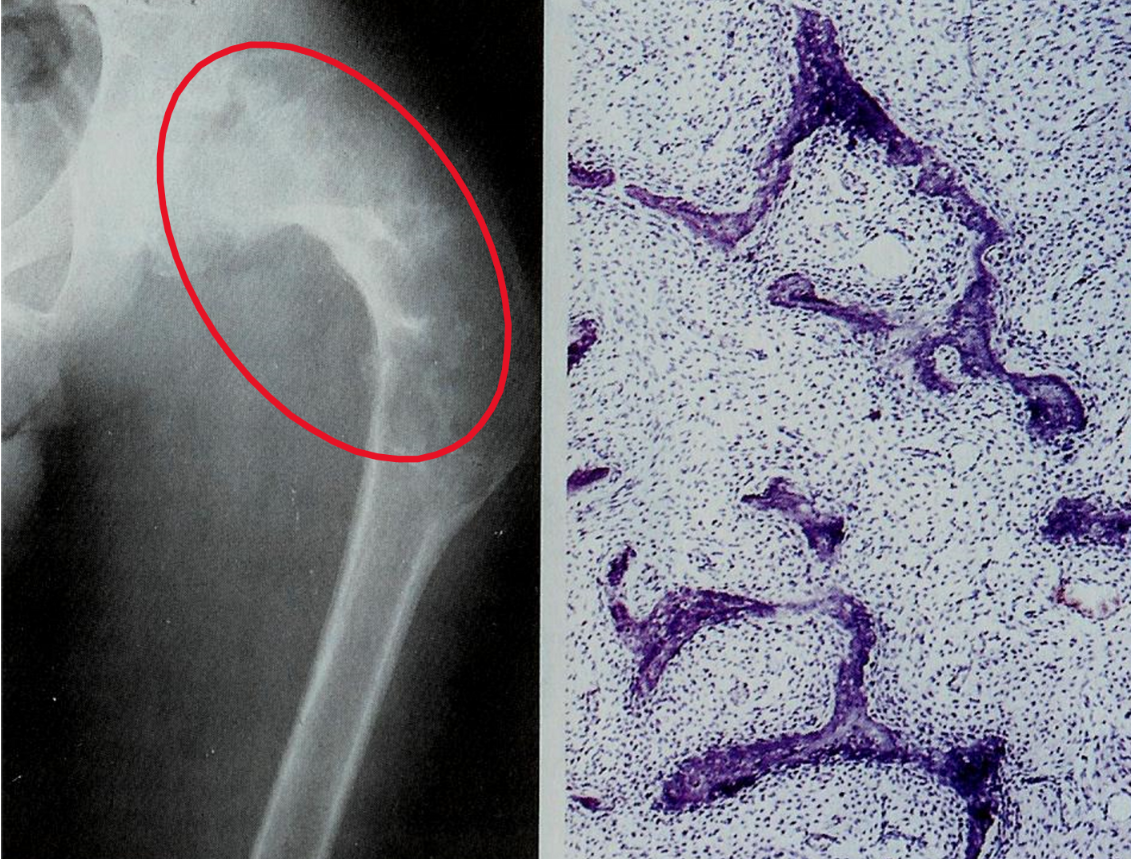

fibrous dysplasia

localized area of disordered maturation of woven bone with fibrous tissue (fibroblasts)

may be polyostotic or monostotic

curvilinear bony spicules shaped like Chinese figure surrounded by fibroblasts seen on biopsy

manifestations results from a somatic gain-of-function mutation during development in GNAS1 (gene that is also mutated in pituitary adenomas)

fibrous dysplasia - monostotic

localized area of disordered maturation of woven bone with fibrous tissue that involves the femur, tibia, ribs, humerus, etc.

frequently asymptomatic

fibrous dysplasia - polyostotic

localized area of disordered maturation of woven bone with fibrous tissue that involves the femur, skull, tibia, ribs, humerus, ribs, fibula, radius, ulna, mandible, & vertebrae

may progress to crippling deformities & fractures